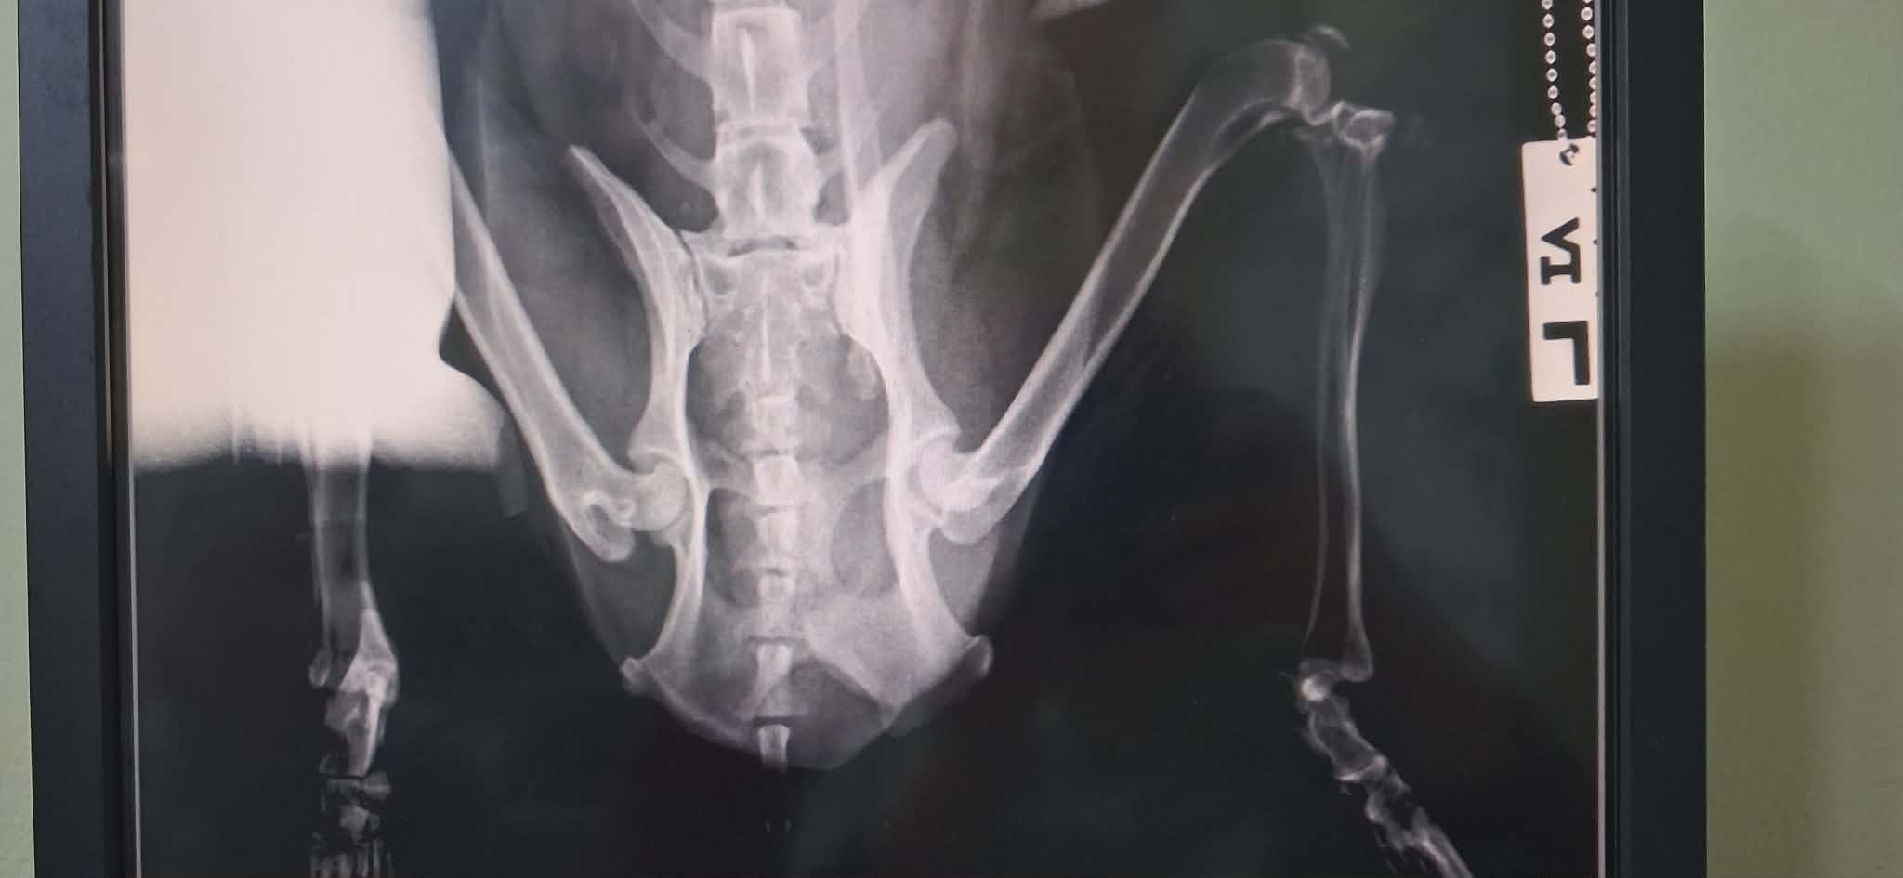

Bei den Untersuchungen zeigte sich, dass Milos Hinterbeine grundsätzlich beweglich sind und er Schmerzempfindungen in der Hinterhand wahrnimmt – ein wichtiges positives Zeichen. Im Röntgen wurden Brüche im Beckenbereich festgestellt, die jedoch Knochen betreffen, welche nicht das Hauptkörpergewicht tragen. Diese Verletzungen allein erklären seine aktuellen Einschränkungen somit nicht vollständig. Die Tierärzte vermuten zusätzlich eine Beteiligung des Rückenmarks oder der Wirbelsäule infolge des Traumas, eine weiterführende Diagnostik (CT/MRT) ist vor Ort jedoch leider nicht möglich. Aktuell wird Milo konservativ behandelt und erhält medizinische Versorgung sowie viel Ruhe. Ob und in welchem Umfang sich seine Bewegungsfähigkeit weiter verbessern wird, lässt sich derzeit nicht sicher vorhersagen. Was aktuell positiv zu bewerten ist: Die Sensibilität in der Hinterhand ist vorhanden, die Hinterbeine sind beweglich, es gibt keine vollständige Lähmung und der Kot- und Urinabsatz funktionieren normal. Milo zeigt sich lebensfroh und aufmerksam. All diese Faktoren geben vorsichtige Hoffnung auf weitere Fortschritte – hier wird die Zeit zeigen, was möglich ist.